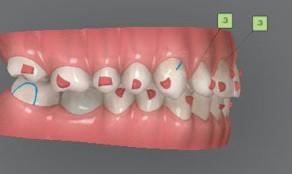

След диагностиката бяха направени екстра- и интраорални снимки, както и рентгенографии; професионалното почистване бе от изключителна важ ност, бяха дадени и инструкции за лич на орална хигиена. Бе направено интра орално сканиране с Medit i500. Цялата тази информация бе използ вана в приложението Smilecloud за 2D биометричен дизайн. В приложението са налични естест вени форми на зъбите и щом бяха под брани зъби и бе направен дизайн

библиотеката на Exocad. Струва си да се отбележи, че 2D дизайнът от Smile Cloud бе спазен до последния детайл в Exocad smile creator с цел да се създаде 3D obj файл със зъбните форми. След като естетичният дизайн бе готов в model creator модула на Exocad, адитивен 3D мок-ъп модел бе експорти ран и принтиран от принтер Formlabs 3. Моделът бе използван за направата на силиконов водач, за да се изготви мо тивационен мок-ъп в устата на паци ента и да се оценят естетичните па раметри. След като пациентът одобри вида на усмивката си, мок-ъпът бе използван за финализиране дизайна на усмивка та. Мок-ъпът бе използван също така като водач по време на мекотъканна та хирургия, както и при препарация на зъбите.

Препарираните зъби бяха импорти рани в Exocad и насложени върху ес тествените форми от биометричния дизайн, като така стана ясно дали зъ бите са били препарирани коректно. По този начин зъболекарят и зъботехни кът работят в една и съща екосистема и резултатът е оптимален. С короната се справихме чрез диги тална редукция на циркония в Exocad, като по този начин на практика създа дохме циркониево кепе, след което про изведохме фасета от IPS Empress Cad Multi. Кепето от Katana Zirconia на зъб 12 с букално послойно нанесена керами ка бе фрезовано (послойното нанасяне бе направено, за да се подобри връзката и да се осигури адхезивно циментиране на фасетата към циркониевото кепе, както и за да се напасне цветът към този на съседните зъби). При първото сканиране регистрирах ме цялата горна зъбна дъга, така че, ко гато се наложи да сканираме повторно, бе изтрит и сканиран наново само зъб 12, тъй като венците не бяха отдръп нати при второто сканиране.

НА

рентгенографии. Инициална терапия и професионално почистване. Интраорално сканиране с цел диги тално планиране. Регистрация и 3D ориентиране на ок лузалната равнина на горна и долна челюст в пространството. 2D дигитално планиране и дизайн на усмивката посредством приложение то Smile Cloud. 3D дигитално планиране и дизайн на функционалните и естетичните па раметри. 3D дигитален дизайн и адитивен мокъп на горна челюст. 3D принтиране и мок-ъп модели. Мотивационен мок-ъп. Фини корекции за постигане на фи налния дизайн. Мекотъканна хирургия с мок-ъпа като водач Препарация през мок-ъпа, използвай ки дизайна като водач за финалната препарация в Exocad. Циркониево кепе ще бъде циментира но с цел адхезивно залепяне на фасе та на края. Кепето има същия цвят като този на съседните зъби, за да може фасетата да се впише перфект но в цялостната усмивка. Изработване на 12 IPS Empress Cad Multi фасети с послойно нанесена ке ТОТАЛНА РЕХАБИЛИТАЦИЯ НА УСМИВКАТА С ИЗЦЯЛО ДИГИТАЛЕН ПРОТОКОЛ Д-р Калин Маринов и зт. Стефан Петров рамика букално върху зъбните препа рации и върху първичното циркони ево кепе (има възможност за ецване и адхезивно

Една седмица след препарацията на зъбите и циментирането на цирко ниевото кепе бяха изработени 12 IPS Empress Cad Multi фасети. Макро- и микротекстурата на фасе тите бяха направени на ръка, след кое то бяха нанесени 3D характеризации с боички, а полирането отново бе напра вено ръчно, за да им се придаде естест вен и естетичен вид. Предизвикателството тук беше короната да има същите оптични характеристики като тези на остана лите зъби при естествена светлина, през поляризационен и флуоресцентен филтър. 3D принтерът бе Fromlabs, софтуерът за фрезоване – Mill Box, а фрез апаратът –imes icore CORiTEC 350i. В крайна сметка постигнахме ес тествен вид на усмивката с натурал на зъбна морфология при изцяло диги тален протокол, при който дизайнът бе направен първоначално и през всич ки етапи на лечението се придържахме към него до самия край Излишно е да отбелязваме, че всички сме удовлетворени от постигнатото! Преди След Победител в категория „Клиничен случай с изцяло дигитален протокол“ в конкурса „Усмивка на годината 2022“